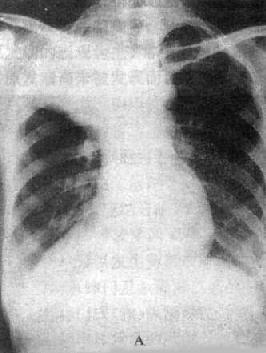

粟粒型肺结核病灶小,透视常难以辩认,故拟诊急性粟型肺结核时应摄片检查。病变早期整个肺野可呈毛玻璃样密度增高。约10日后可出现均匀分布的1.5~2mm大小、密度相同的粟粒状病灶,正常肺纹理常不能显示(图3-1-22)。经过适当治疗后。病灶可在数月内逐渐吸收,偶尔以纤维硬结或钙化而愈合。病变恶化时,可以发生病灶融合,表现为病灶增大,边缘模糊,甚至形成小片状或大片状影,并可干酪样化而形成空洞。

图3-1-22 急性粟粒型肺结核

两肺野布满粟粒状病灶,分布均匀,肺门大

(2)亚急性或慢性血行播散型肺结核:系少量结核杆菌在较长时间内多次进入血流播散至肺部所致。患者抵抗力较强,症灶多以增殖为主,临床症状可不明显或有反复的发热、畏寒或轻度结核中毒症状如低热、盗汗、无力、消瘦等。